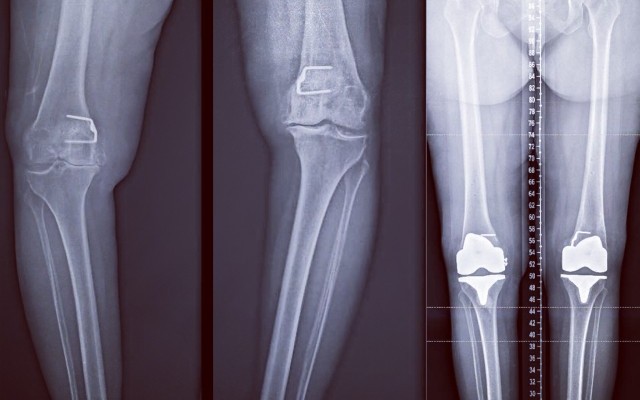

By Dr Kaushik Hazratwala, Orthopaedic Surgeon, Director – Orthopaedic Research Institute of Qld Director – Townsville Lower Limb Clinic Finally, after 15 yrs. this Korean group has proven that Computer Navigation will not improve patient outcome in all comers. The proponents of conventional Knee replacements will rejoice in this publication and uncork expensive French...Platelet Rich Plasma (PRP) - Latest Evidence or Lack of !!!

Alternate alignment is gaining popularity amongst orthopaedic surgeons. The alternate alignment principal for total knee is based on the gap balancing principal, allowing the medial and lateral soft tissue envelope to remain at their native lengths.12 It is an anatomical tibia 1st technique with subsequent femoral cuts to balance the knee within its native soft tissue envelope, Compared to...Lateral Hip Pain (Outer)

Total knee replacement has a very high success rate in relieving pain and bearing upon the ability to mobilize. Overall, 95% of these operations are highly successful and we know that at 10 – 15 years after the surgery 95% are still working very comfortably. In general, the knee replacement will last longer in older and lighter people. 1. Care your knee after knee replacement It will take...Is Hip replacement the best option for hip pain?

If you are considering a Total Knee Replacement or are having one soon, this video will help you understand what the surgeon will be doing. I should clarify that I no longer use rods inserted into the tibia and the femur as I use computer navigation. I do use bone cement to fix the implants to your bone. My patients usually stay in the hospital for 2 days and are walking the same day of the...Total Knee Replacement vs Resurfacing

With the invent of new surgical techniques and instruments Knee Replacements can now be performed almost like Resurfacing. Taking as little bone as possible and resurfacing it with the equal amount of metal and plastic. Total Knee Replacement vs resurfacing The attached picture is from a knee arthroplasty I performed today. This is the actual picture of the bone cuts I performed on the...Baker's Cyst of The Knee

Many patients suffer from arthritis in 2 large joints at the same time that require joint replacement. Patients usually think that having 2 large joints replaced at the same time would require prolonged rehabilitation and increased pain. THIS IS NOT TRUE. Nowadays with advanced surgical techniques and postoperative pain relief protocols, patients are only a day longer in hospital, and...ACL rupture and associated structural injuries of the knee

It is important to understand that there are multiple bony cuts that are delicately balanced with each other so that the knee moves in a balanced fashion on both sides, and the patient does not feel insecure or unstable. I have created my own surgical technique for knee replacement that intricately predicts the ligament balance and accommodates the bony cuts to fit the ligament envelope. I...